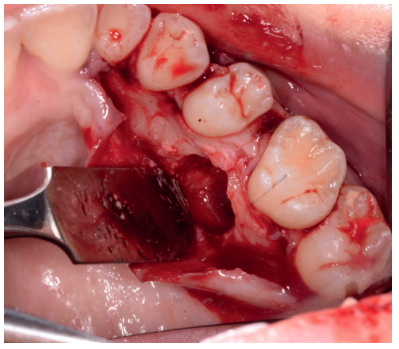

Caso clínico: se presenta un caso clínico de una mujer de 20 años, sin antecedentes médico-quirúrgicos de interés, que acudió a consulta remitida por su ortodoncista, para la extracción de un premolar maxilar retenido, en posición invertida. Tras la extracción del premolar y del tercer molar inferior retenidos, se obtuvo dentina procedente de ambos, para la regeneración ósea guiada del defecto resultante de la extracción del premolar, realizando revisiones a la semana y a los 4 meses de la intervención.

Clinical case: a clinical case of a 20-year-old woman is presented, with no interesting medical record, who went to dental clinic for removal of an inverse maxillary bicuspid retained. After maxillary bicuspid and lower third molar extractions, autogenous dentin was obtained from both teeth, to perform a guided bone regeneration of the bicuspid defect. A week and 4-month check-up were carried out.

El objetivo de este caso clínico es presentar la eficacia de la dentina autógena como material de injerto en un procedimiento de ROG, tras la exodoncia de un premolar superior izquierdo retenido, en posición invertida.